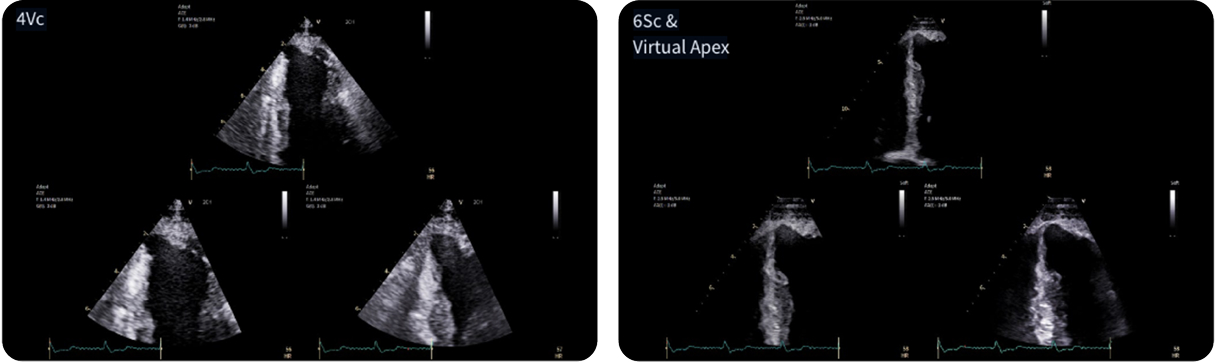

Fifty shades of grey

Caso condiviso da Marcello De Santis